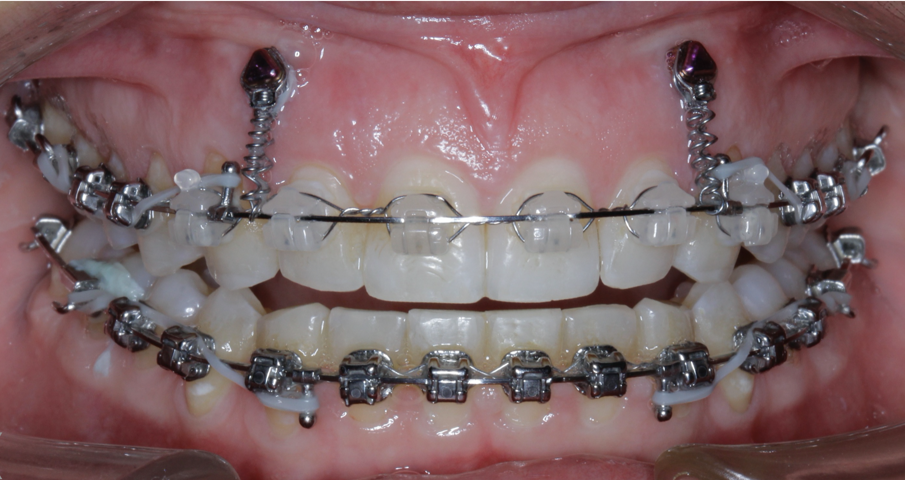

TADs are placed at the second visit with a 14 × 25 mm copper (Cu) and nickel–titanium (NiTi) wire and are tied from the anchor to the wire with an elastic thread (surgical thread; Fig. 6). Once the patient has progressed to larger Cu–NiTi wires and stainless steel, the TADs are tied to the wire using a power chain looped to the wire, or NiTi closing springs, depending on the thickness of the tissue (Figs. 7 & 8).

Once the intrusion has been completed, the TADs are tied to the wire and vertical elastics are used to close the bite without relapse of the intrusion. If buccal crown tip is seen, owing to the movement created by the intrusion, a power chain torquing sling is used to encourage lingual crown tipping and to prevent flaring of the incisors (Fig. 9). Once the case has been completed, the appliance is removed and a gingivectomy is performed to idealise the tissue shape and the final contours are made to the hard tissue (Figs. 10–12, end of treatment).